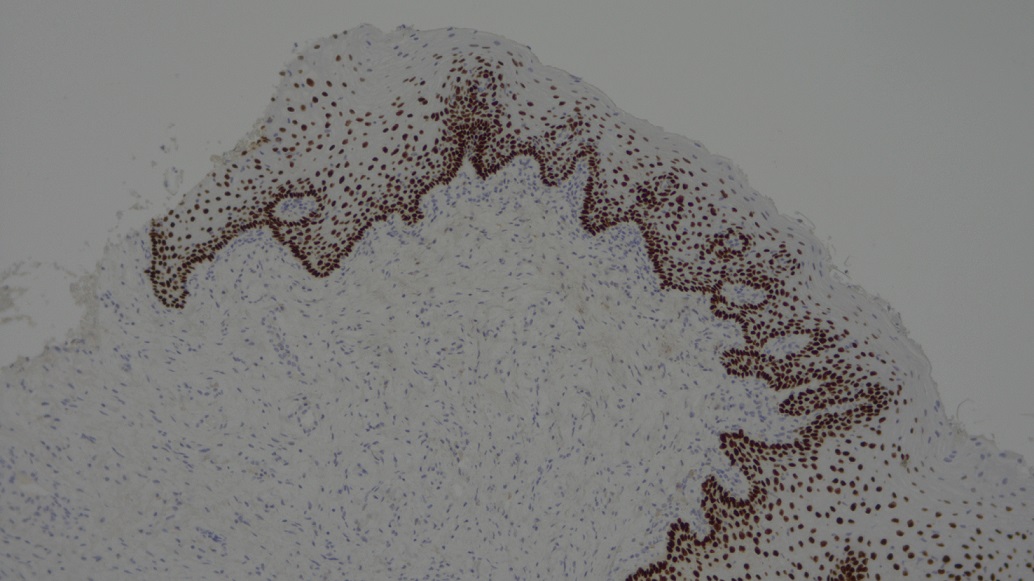

Categoría: Microscópica

2do lugar: Esteban Gordón / Foto: Expresión de la proteína p63.